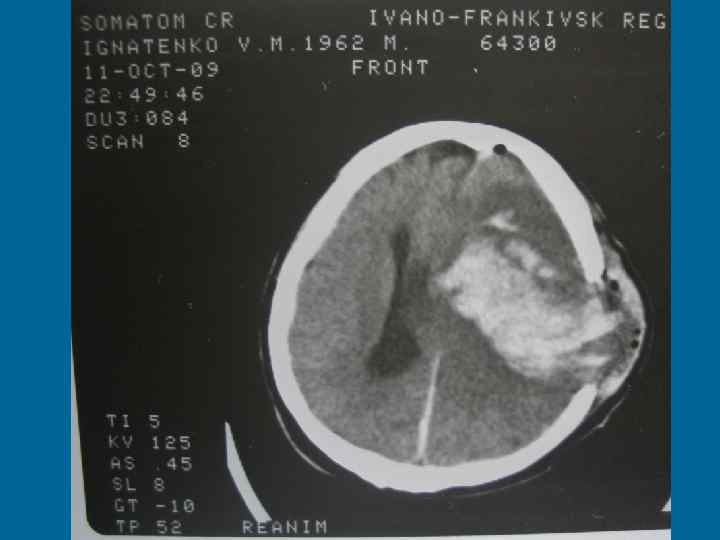

А. Центрогенна ДН • Виникає при травмах та захворюваннях головного мозку, стисненні та дислокації його стовбура, в ранньому періоді після клінічної смерті, при деяких інтоксикаціях (опіати, барбітурати), порушенні аферентної імпульсації. • Яскравий клінічний симптом центрогенної ГДН – порушення ритму дихання або поява патологічних ритмів (т. Чейна-Стокса – характерно для ураження переднього мозку), центральна нейрогенна гіпервентиляція (пошкодження гіпоталамуса), апнейтичне та групове періодичне дихання (пошкодження нижніх відділів покришки мозку), дихання Біота або атактичне дихання (пошкодження верхніх відділів стовбура), гаспінг-дихання (при пошкодженні довгастого мозку та в агональному періоді). • Синдром “проклятия Ундины” – одна з форм центрогенних порушень дихання через втрату дихального автоматизму із збереженим умовним контролем.